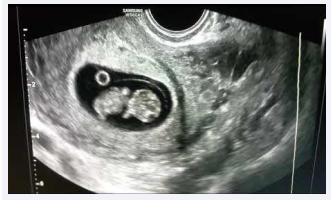

• Our study demonstrates that the second foetus can be affected by many causes (development of placenta, uterine contractions, but also extraction obstetrical manoeuvres), and in consideration thereof we sustain caesarean delivery in the case of twin pregnancies (Figure 1).

Demonstrates that the second foetus can be affected by  many causes

Figure 1: Demonstrates that the second foetus can be affected by many causes.